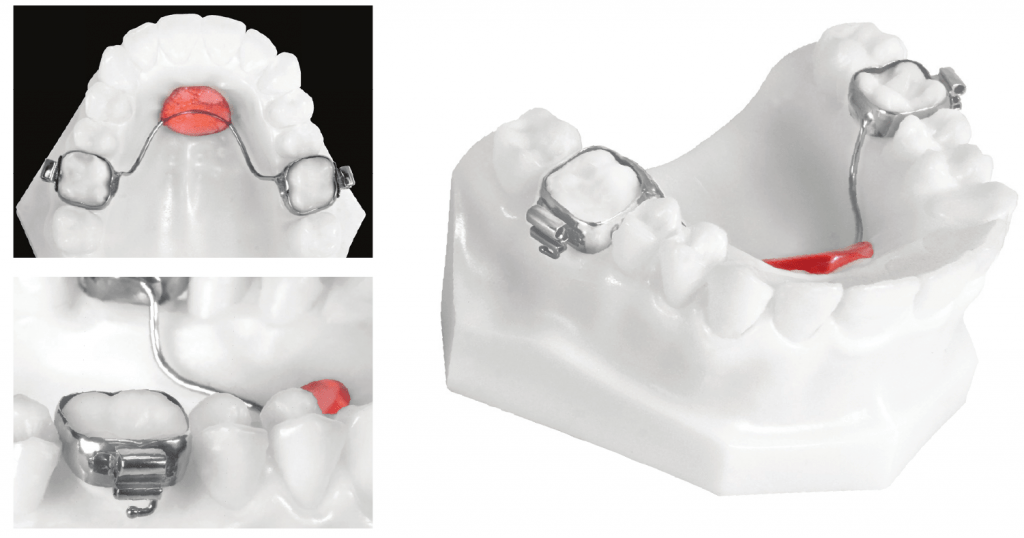

Nance (or transpalatal) appliance – used when there is bilateral premature loss of deciduous teeth. This appliance uses the soft tissue in rugae area as a brace to prevent the first molars from rotating and drifting mesially. This is a maxillary appliance (only) and can be utilized for anchorage.

Partial denture – can be used as a space maintainer, while also improving aesthetics and function.